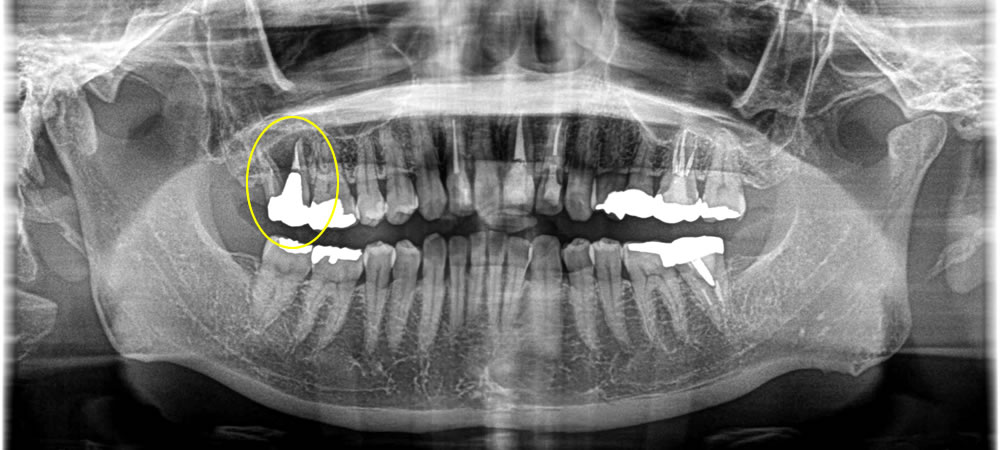

歯根破折のため抜歯しインプラントで修復した症例

年齢

40代

性別

女性